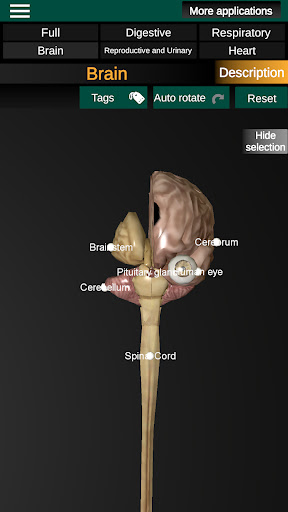

Internal Organs in 3D Anatomy لـ Vodafone Smart N9 Lite

(الأجهزة الداخلية في)

Internal Organs 3D Anatomy 3.4

يمكنك هنا تنزيل ملف حزمة تطبيق أندرويد "Internal Organs 3D Anatomy" الخاصة بجهازVodafone Smart N9 Lite مجانًا، نسخة ملف حزمة تطبيق أندرويد - 3.4 للتحميل على Vodafone Smart N9 Lite اضغط ببساطة على هذا الزر. إنه سهل وآمن. نحن نقدم فقط ملفات حزمة تطبيق أندرويد الأصلية. إذا انتهكت أية مواد موجودة في الموقع حقوقك قم بإبلاغنا من خلال